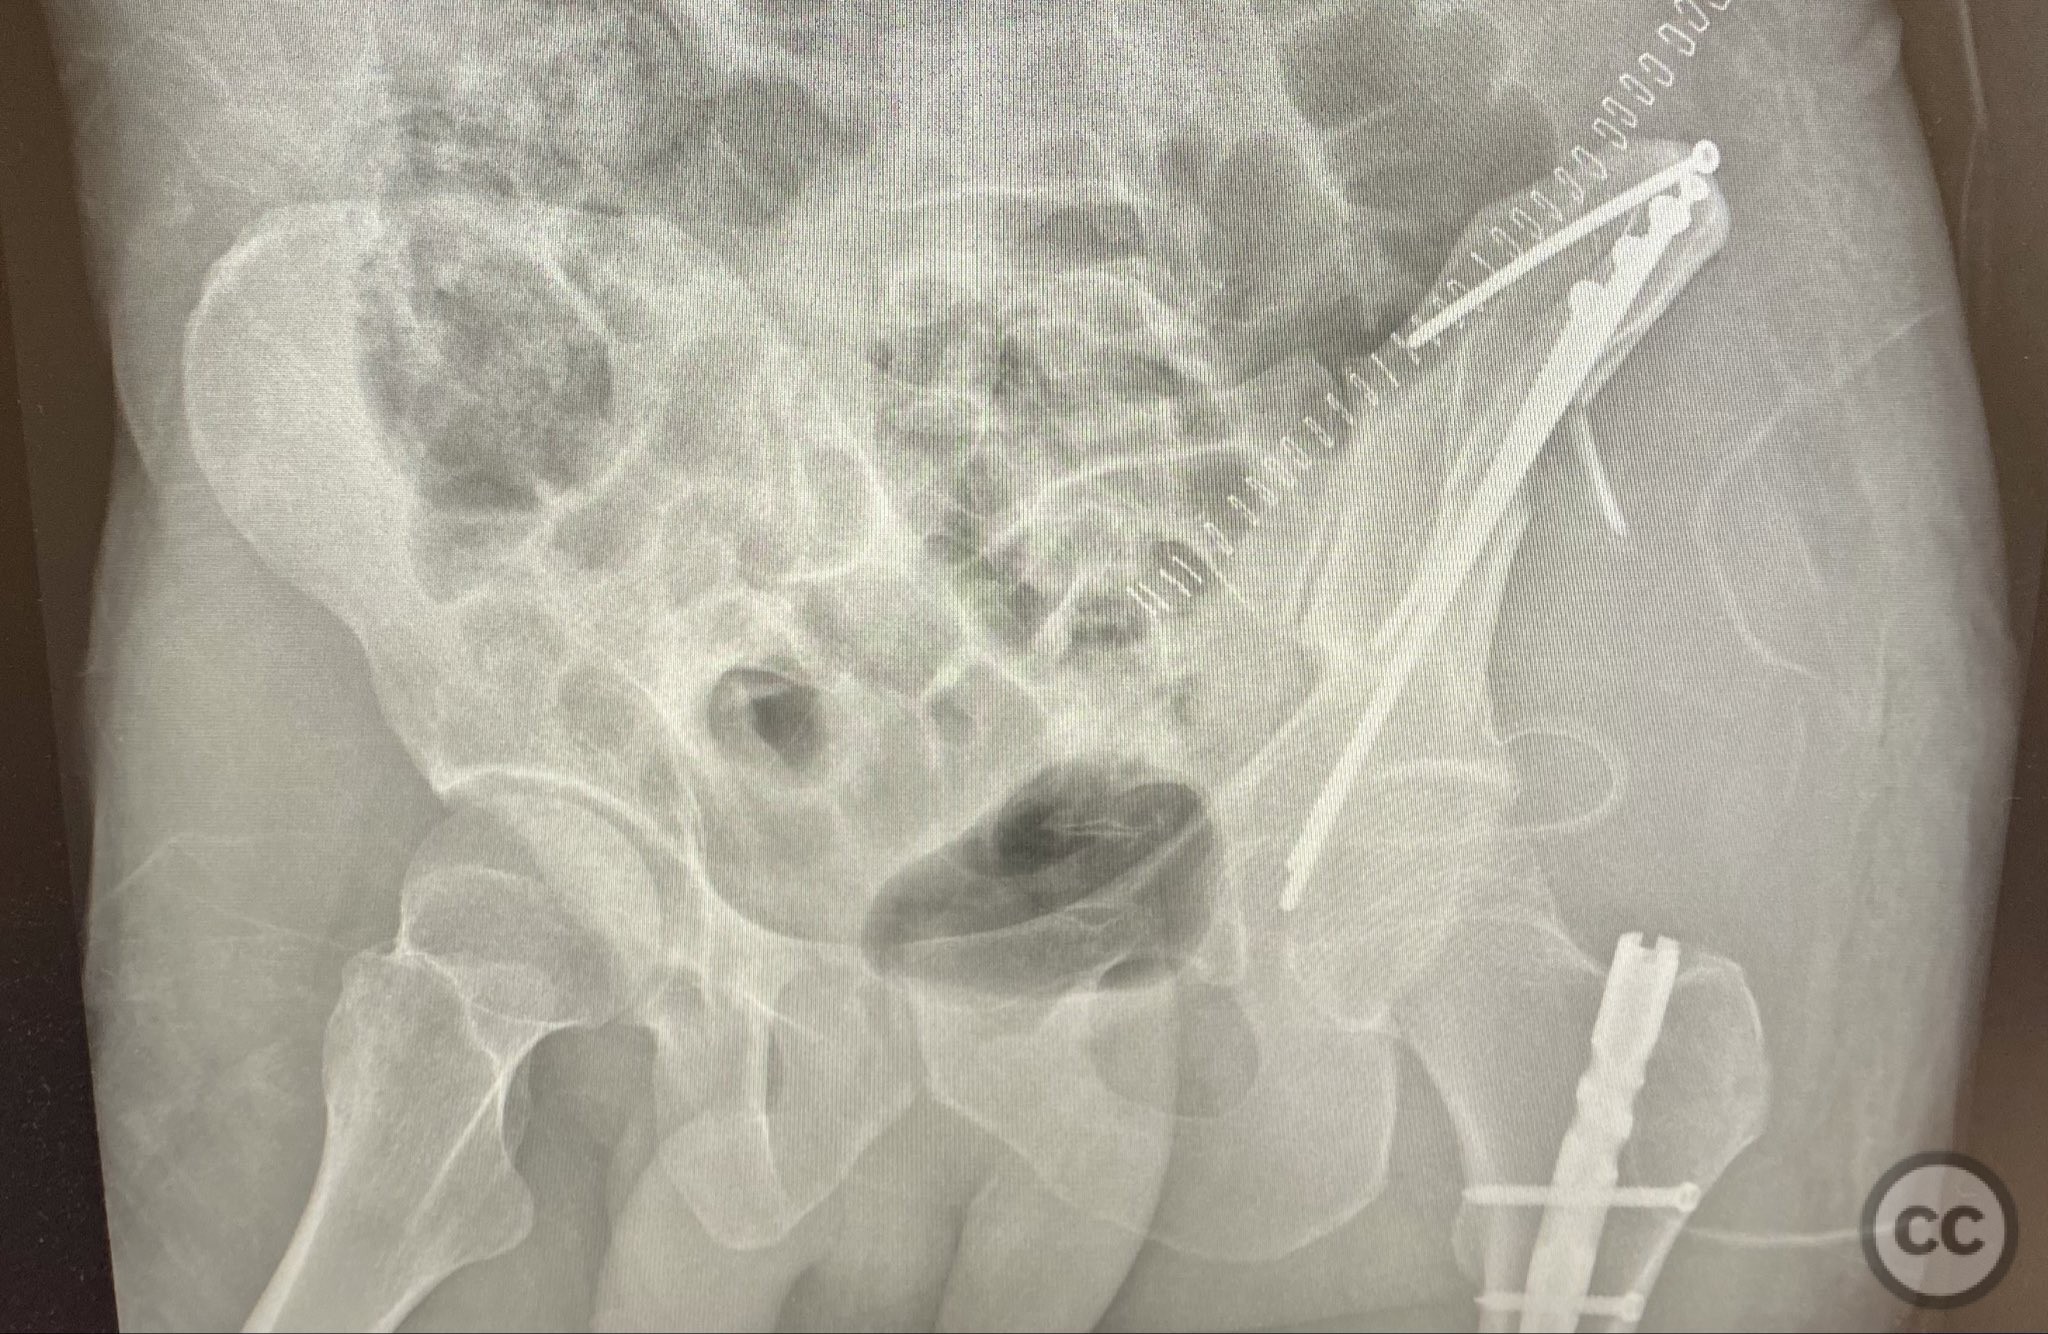

Clinical and radiological findings:  A patient sustained a high-energy injury resulting in an open, comminuted fracture of the iliac wing, sparing the pelvic ring. Associated injuries included spine, rib, and femur fractures. Initial radiographs and axial CT imaging demonstrated significant comminution of the iliac wing with intraosseous air densities indicative of an open wound. No pelvic ring disruption was identified. AO/OTA classification: 61-A2. The presence of multiple associated injuries is consistent with a direct lateral load mechanism.

Orthopaedic implants used:   4.5mm cortical lag screws, 3.5mm cortical lag screws